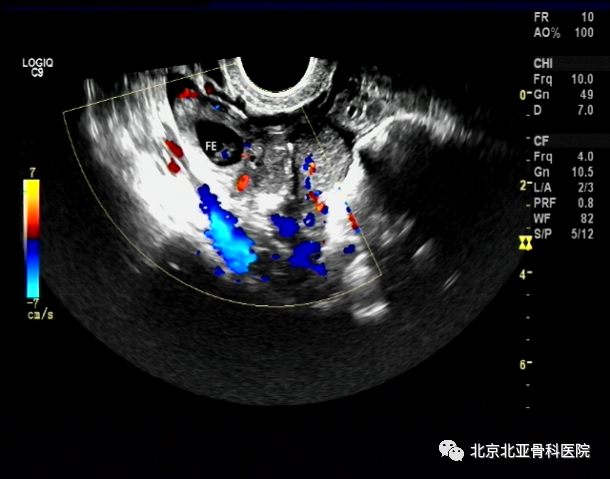

输卵管是指在B超检查中,可以看到输卵管。导致输卵管堵塞的原因有多种,比如输卵管堵塞、输卵管内膜粘连、受精卵 不在宫腔内、以及受精卵运行受阻等,对女性的影响较大。如果出现了输卵管堵塞,则应该积极治疗。